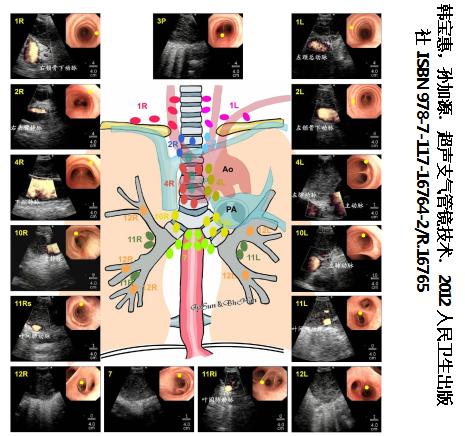

1. 超声支气管镜下淋巴结定位和命名的标准化

上海市胸科医院制订的超声支气管镜下淋巴结定位模式图